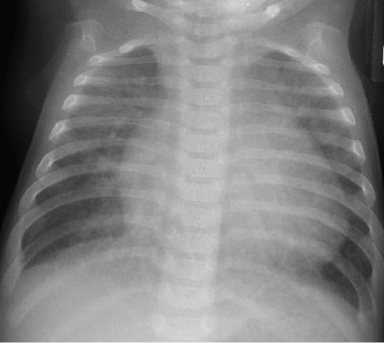

- A chest radiograph: cardiomegaly, narrow mediastinum, and increased pulmonary vasculature. ECG: RAD and RVH

Imaging

- Small to N cardiac silhouette

- Decrease pulmonary vasculature